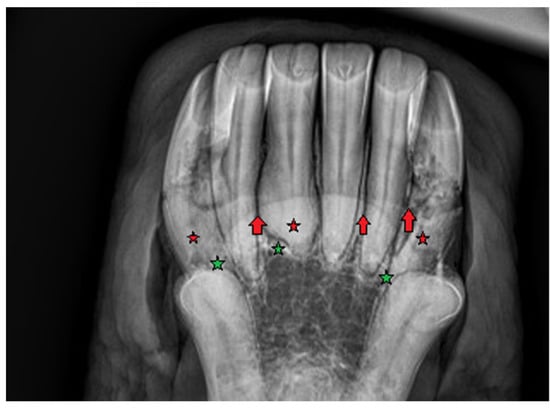

2.1.1. Case 1

2.1.2. Case 2